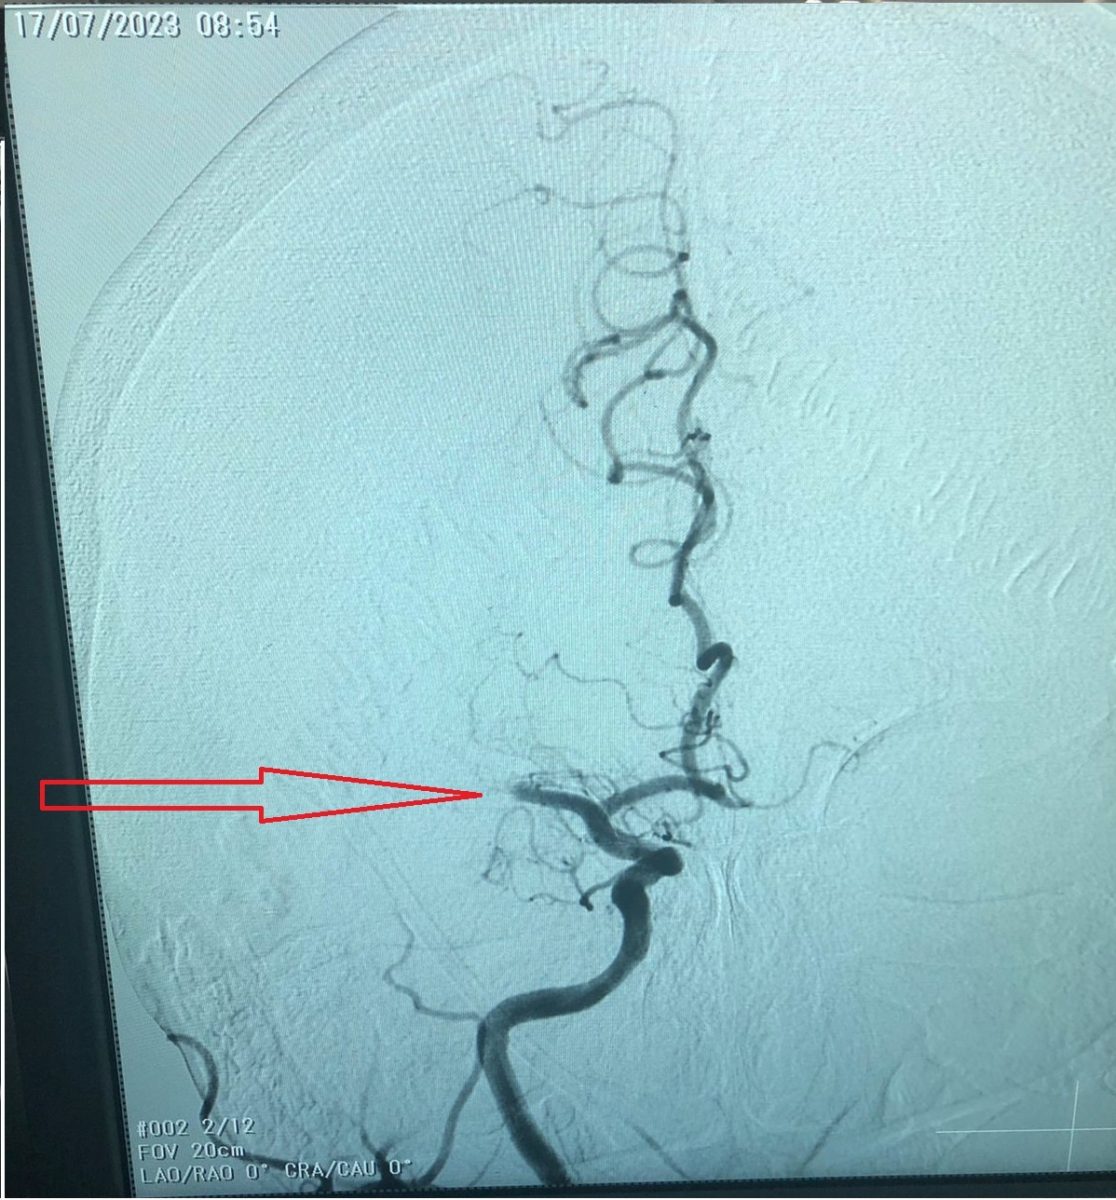

Женщине в экстренном порядке с диагностической целью были проведены КТ головного мозга, КТ — ангиография магистральных сосудов шеи, головного мозга, благодаря которым врачи выявили точное место перекрытия сосуда тромбом – район средней мозговой артерии.

В этот же день пациентке провели операцию. Хирурги удалили тромб через артерию.